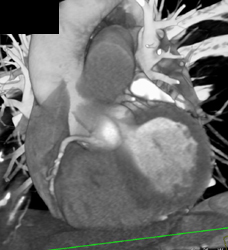

Diagnosis

Stent in LAD and It Is Patent